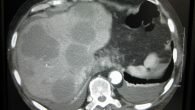

Онкологические заболевания тяжелой формы, обычно на 3—4-й стадии, характеризуются обширной зоной распространения. Метастазы в печени усугубляют положение пациента. Это своеобразный маркер рака и терминальной (последней) стадии развития. Используют методику химиотерапии при значительном распространении раковых клеток. Применение цитостатических лекарств не дает возможности разрастаться раковым клеткам и уменьшает саму опухоль. Современные препараты в основном вводятся непосредственно в артерию. Таблетки и капельницы в вену фактически не применяются, так как имеют много побочных последствий.

Проводится химиотерапия орально (прием таблетированных лекарств) либо введением препаратов внутривенно. Выбираются препараты, которые пагубно воздействуют на зараженные клетки, убивая их. Медикамент быстро переносится кровью к метастазам и начинает свое действие. В современной медицине используют методику химиоэмболизации — введения препарата непосредственно в артерию через катетер. Этот сосуд имеет прямое соединение с печенью. В такой ситуации количество побочных эффектов на порядок ниже и увеличивается возможность введения большей дозы химии. Лечение метастазов в печени такой методикой возможно только в том случае, если орган нормально функционирует. Если же есть проблемы с работой печени — химиотерапия противопоказана.